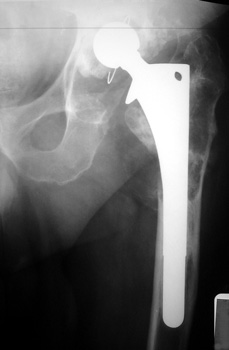

OSTEOLYSIS—ABOUT ACETABULAR COMPONENT GRUEN ZONE II, WITH PATHOLOGIC FRACTURE